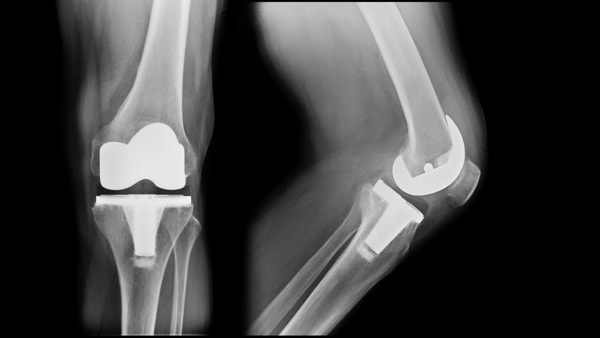

• Knee joint Osteo-arthritis

• Post TKR pain

• Patient medically unfit for Knee replacement

• Chronic Knee pain